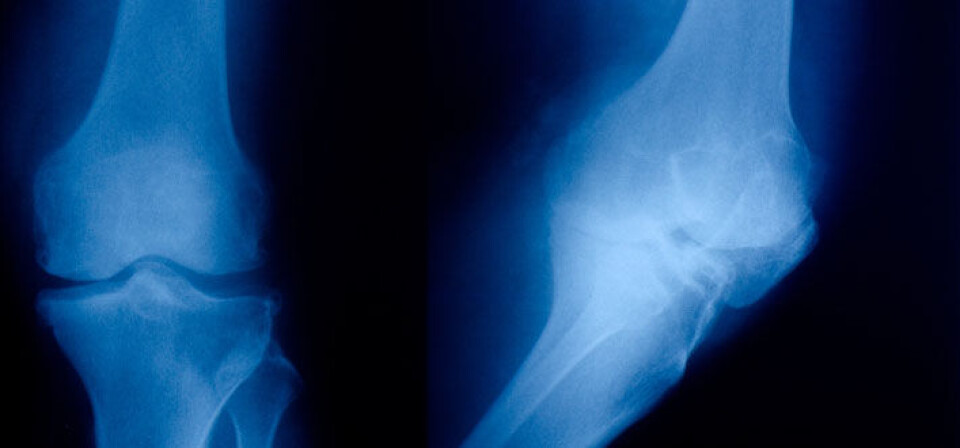

Vektøkning hos personer yngre enn 30 år øker risikoen for å utvikle slitasjegikt (artrose) i kne og hofte.

Risikoen for å utvikle artrose (slitasjegikt), en tilstand som gir smerter og redusert fysisk funksjon, øker med selv en liten økning av vekten.

Vektøkning før fylte 30 år gir ekstra stor risiko for å utvikle alvorlig artrose, men risikoen er mindre hos dem som øker vekten etter 30-årsalder.

Operasjon kan være nødvendig for de mest alvorlige tilfellene av artrose i kne eller hofte. I Norge settes det hvert år inn i underkant av 5000 proteser for alvorlig artrose i kneledd, og mer enn 7000 proteser for alvorlig artrose i hofteledd.